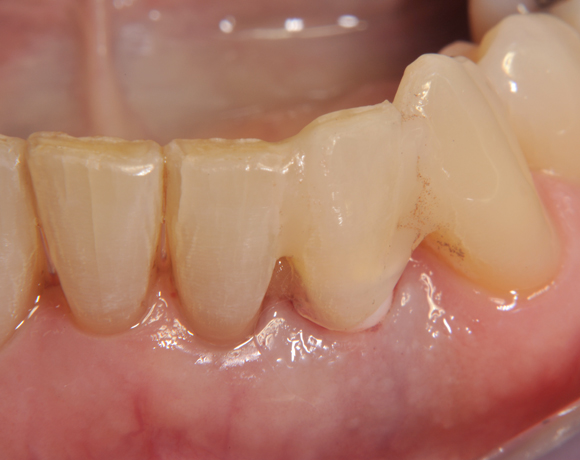

Am Beispiel dieses Patientenfalls wird gezeigt wie ein Einzelimplantat für den Unterkieferfrontzahn 33 eingesetzt wird.